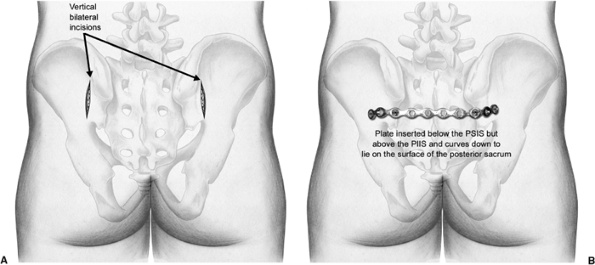

Figure 40.9.

The plate is bent to the iliac wing in situ. It will then be fixed with a bicortical screw directed toward the anterior aspect of the sacroiliac joint. |

Figure 40.10. Schematic drawings of the bilateral skin incisions (A) and the final plate placement on the sacrum and iliac wings (B).

|

on the contralateral side of the pelvis, and a limited portion of the

gluteus maximus is reflected off the erector spinae fascia. A straight

10- or 12-hole, 3.5- or 4.5-mm reconstruction plate is used. The

optimal position of the dorsal tension band plate is just below the

PSIS. This decreases plate prominence and ensures that the screws in

the ilium are anchored in the strong bone of

the

sciatic buttress. The plate is typically inserted from the side of the

open reduction and tunneled through to the contralateral surgical site.

A 1/2-inch osteotome is passed from one incision, ventral to the

erector spinae fascia, osteotomizing the sacral spinous process of S2 (Fig. 40.7). The unbent straight pelvic reconstruction plate is then passed along the same track until visualized in the second incision (Fig. 40.8).

A screw is inserted bilaterally between the tables of the ilium into

the sciatic buttress. Tightening these screws adds tension to the plate

over the dorsum of the sacrum and causes compression of the sacral

fracture. The ends of the plate are then bent to the iliac wing in situ

and secured with a single screw at each end of the plate (Figs. 40.9 and 40.10).